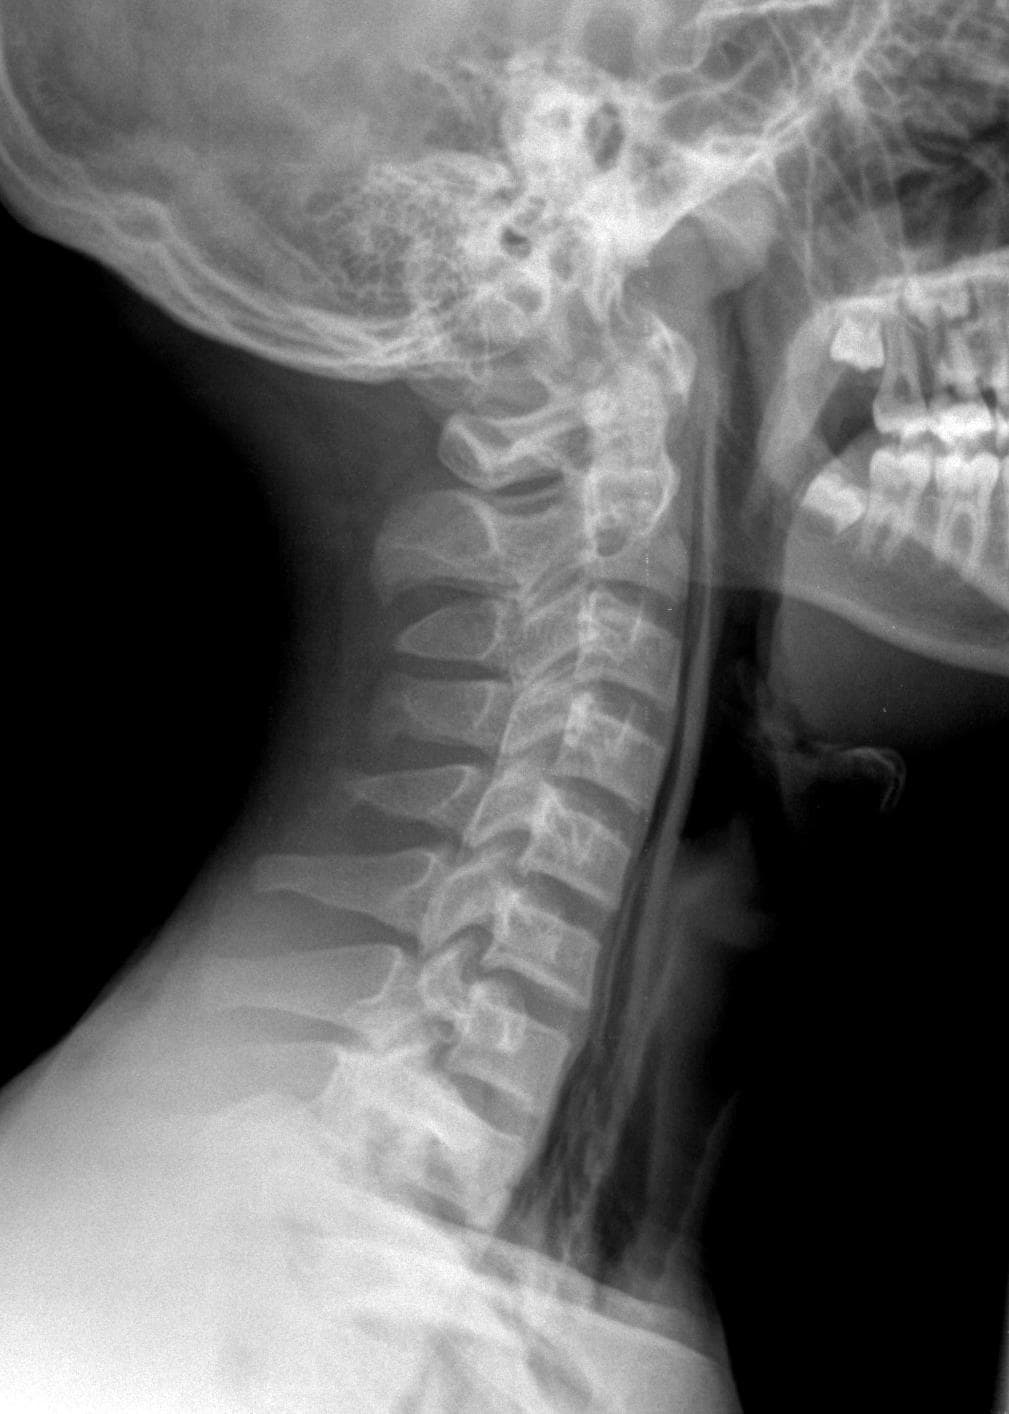

Chest Pain Brought On Or Worsened By Forceful Breathing Is Called Pleuritic Chest Pain 4.This Symptom Typically Originates From An Infection, Injury Or Other Condition Affecting The Right Lung Or Chest Wall.

Pain in the chest while breathing is a condition that happens when a person experiences slightly to intense pain in the chest area when breathing in. The pain may be worse when you cough, sneeze or move around. Why does it hurt in my chest when i inhale?